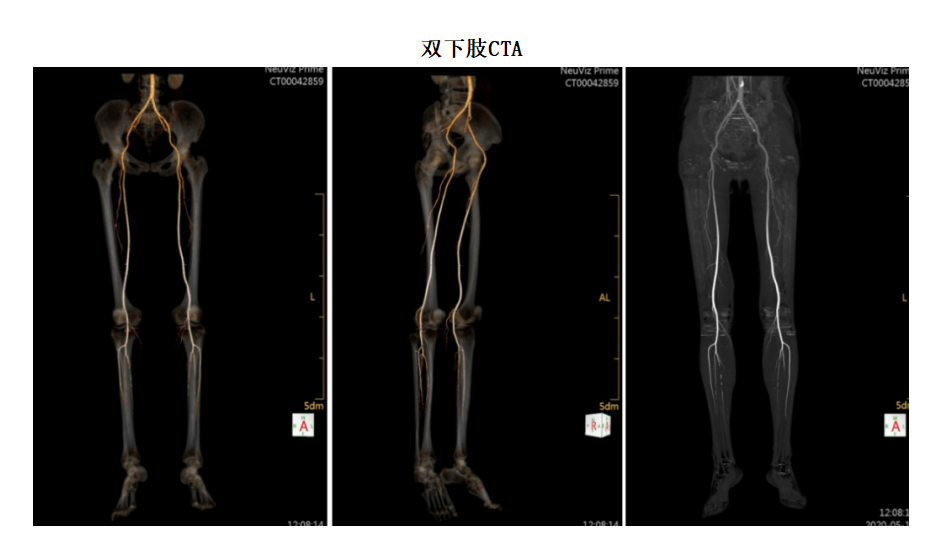

CT血管造影(CTA)检查范围包括冠状动脉、头颈部、肺动脉、主动脉(胸、腹)以及四肢血管造影等。新设备的强大的性能,让本来就很成熟的血管CTA成像与后处理技术更加准确更加便捷。